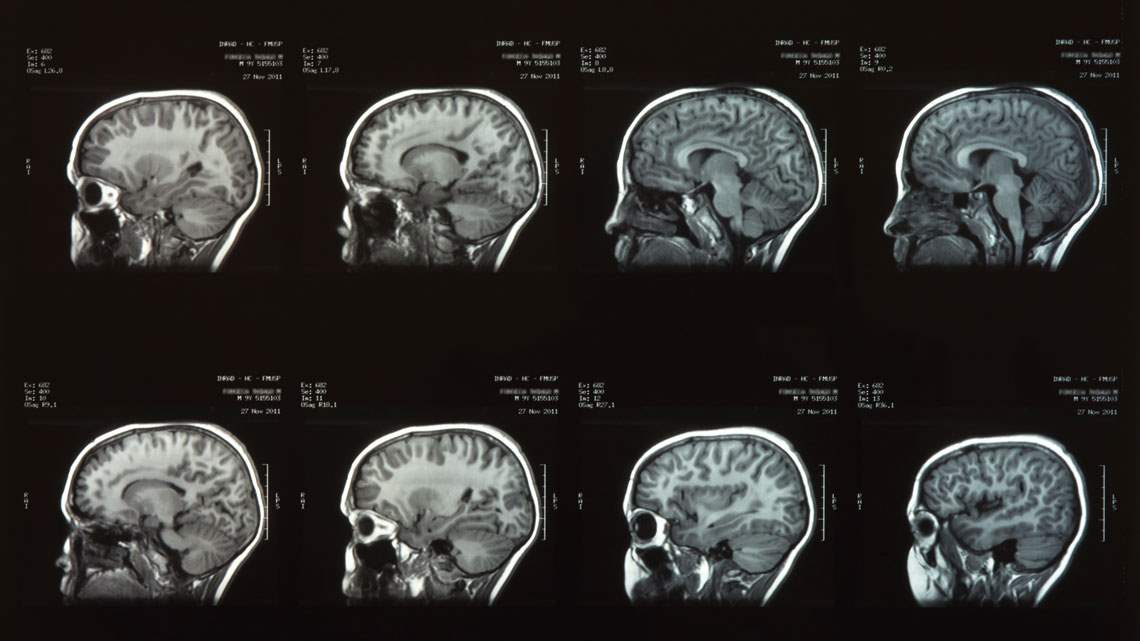

Os cientistas descobriram que a ativação precisa de certos neurônios na amígdala central inibe a percepção da dor.

Nos testes, essa ativação levou os ratos a parar imediatamente com comportamentos de dor, como lamber as patas ou tocar o rosto. A simples desativação desses neurônios reverteu o bloqueio, demonstrando um controle considerável sobre a resposta à dor.

A metodologia utilizada para realizar a ativação e desativação dos neurônios destaca a possibilidade de modulação cerebral como um potente mecanismo de alívio da dor. Este enfoque contrasta com os métodos atuais, que geralmente afetam múltiplas áreas sensoriais e emocionais.

As conclusões do estudo abrem caminhos para o desenvolvimento de medicamentos que possam especificamente ativar esses neurônios, oferecendo alívio da dor sem os efeitos adversos frequentemente associados a anestésicos gerais.

Existem semelhanças entre a pesquisa da Universidade Duke e abordagens médicas atuais, como a estimulação cerebral profunda (DBS) no tratamento da depressão resistente.

Ambas assumem a modulação cerebral para corrigir disfunções neurológicas. Esse alinhamento sugere um novo paradigma em tratamentos de distúrbios relacionados à dor e humor, focando em áreas cerebrais antes não consideradas para tais fins.